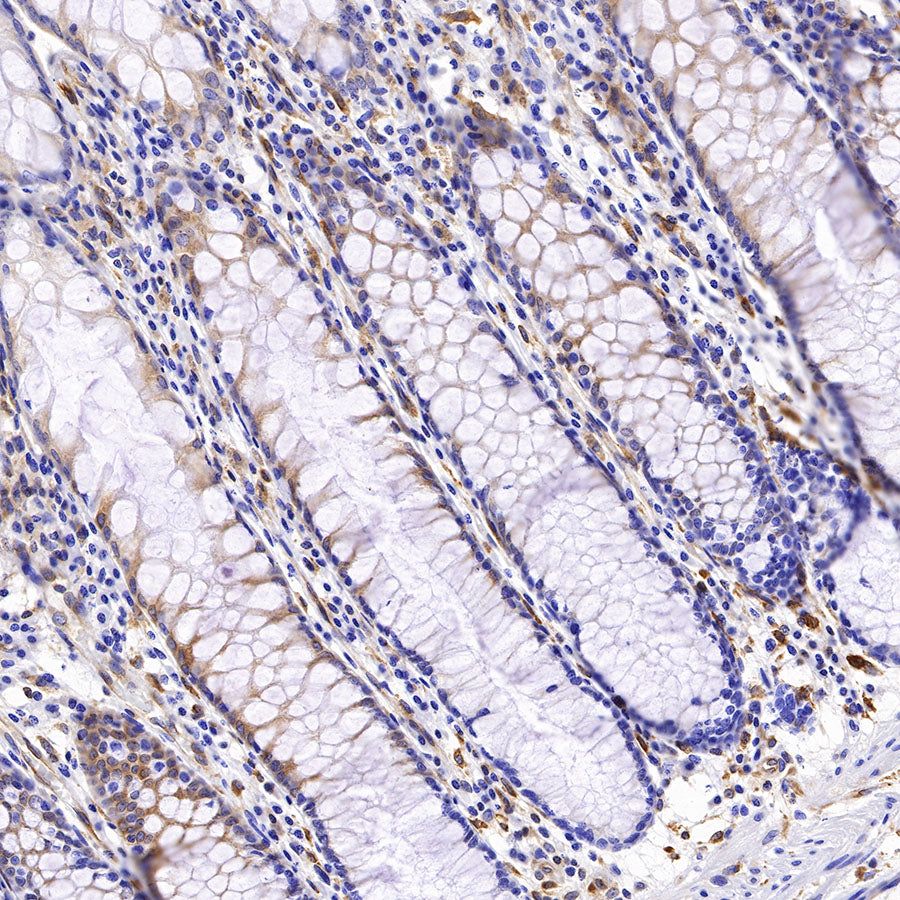

Picture

Picture

Immunohistochemistry